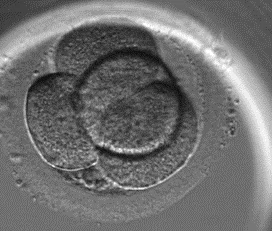

Secondo e terzo giorno: Divisione cellulare regolare

Nei giorni successivi alla fecondazione, si verifica la cosiddetta segmentazione. Ciò significa che le cellule dell’embrione si dividono in modo regolare.

Il secondo giorno, l’embrione si divide regolarmente (stadio di 4 cellule)

Il terzo giorno, l’embrione continua a dividersi regolarmente (stadio di 8 cellule)